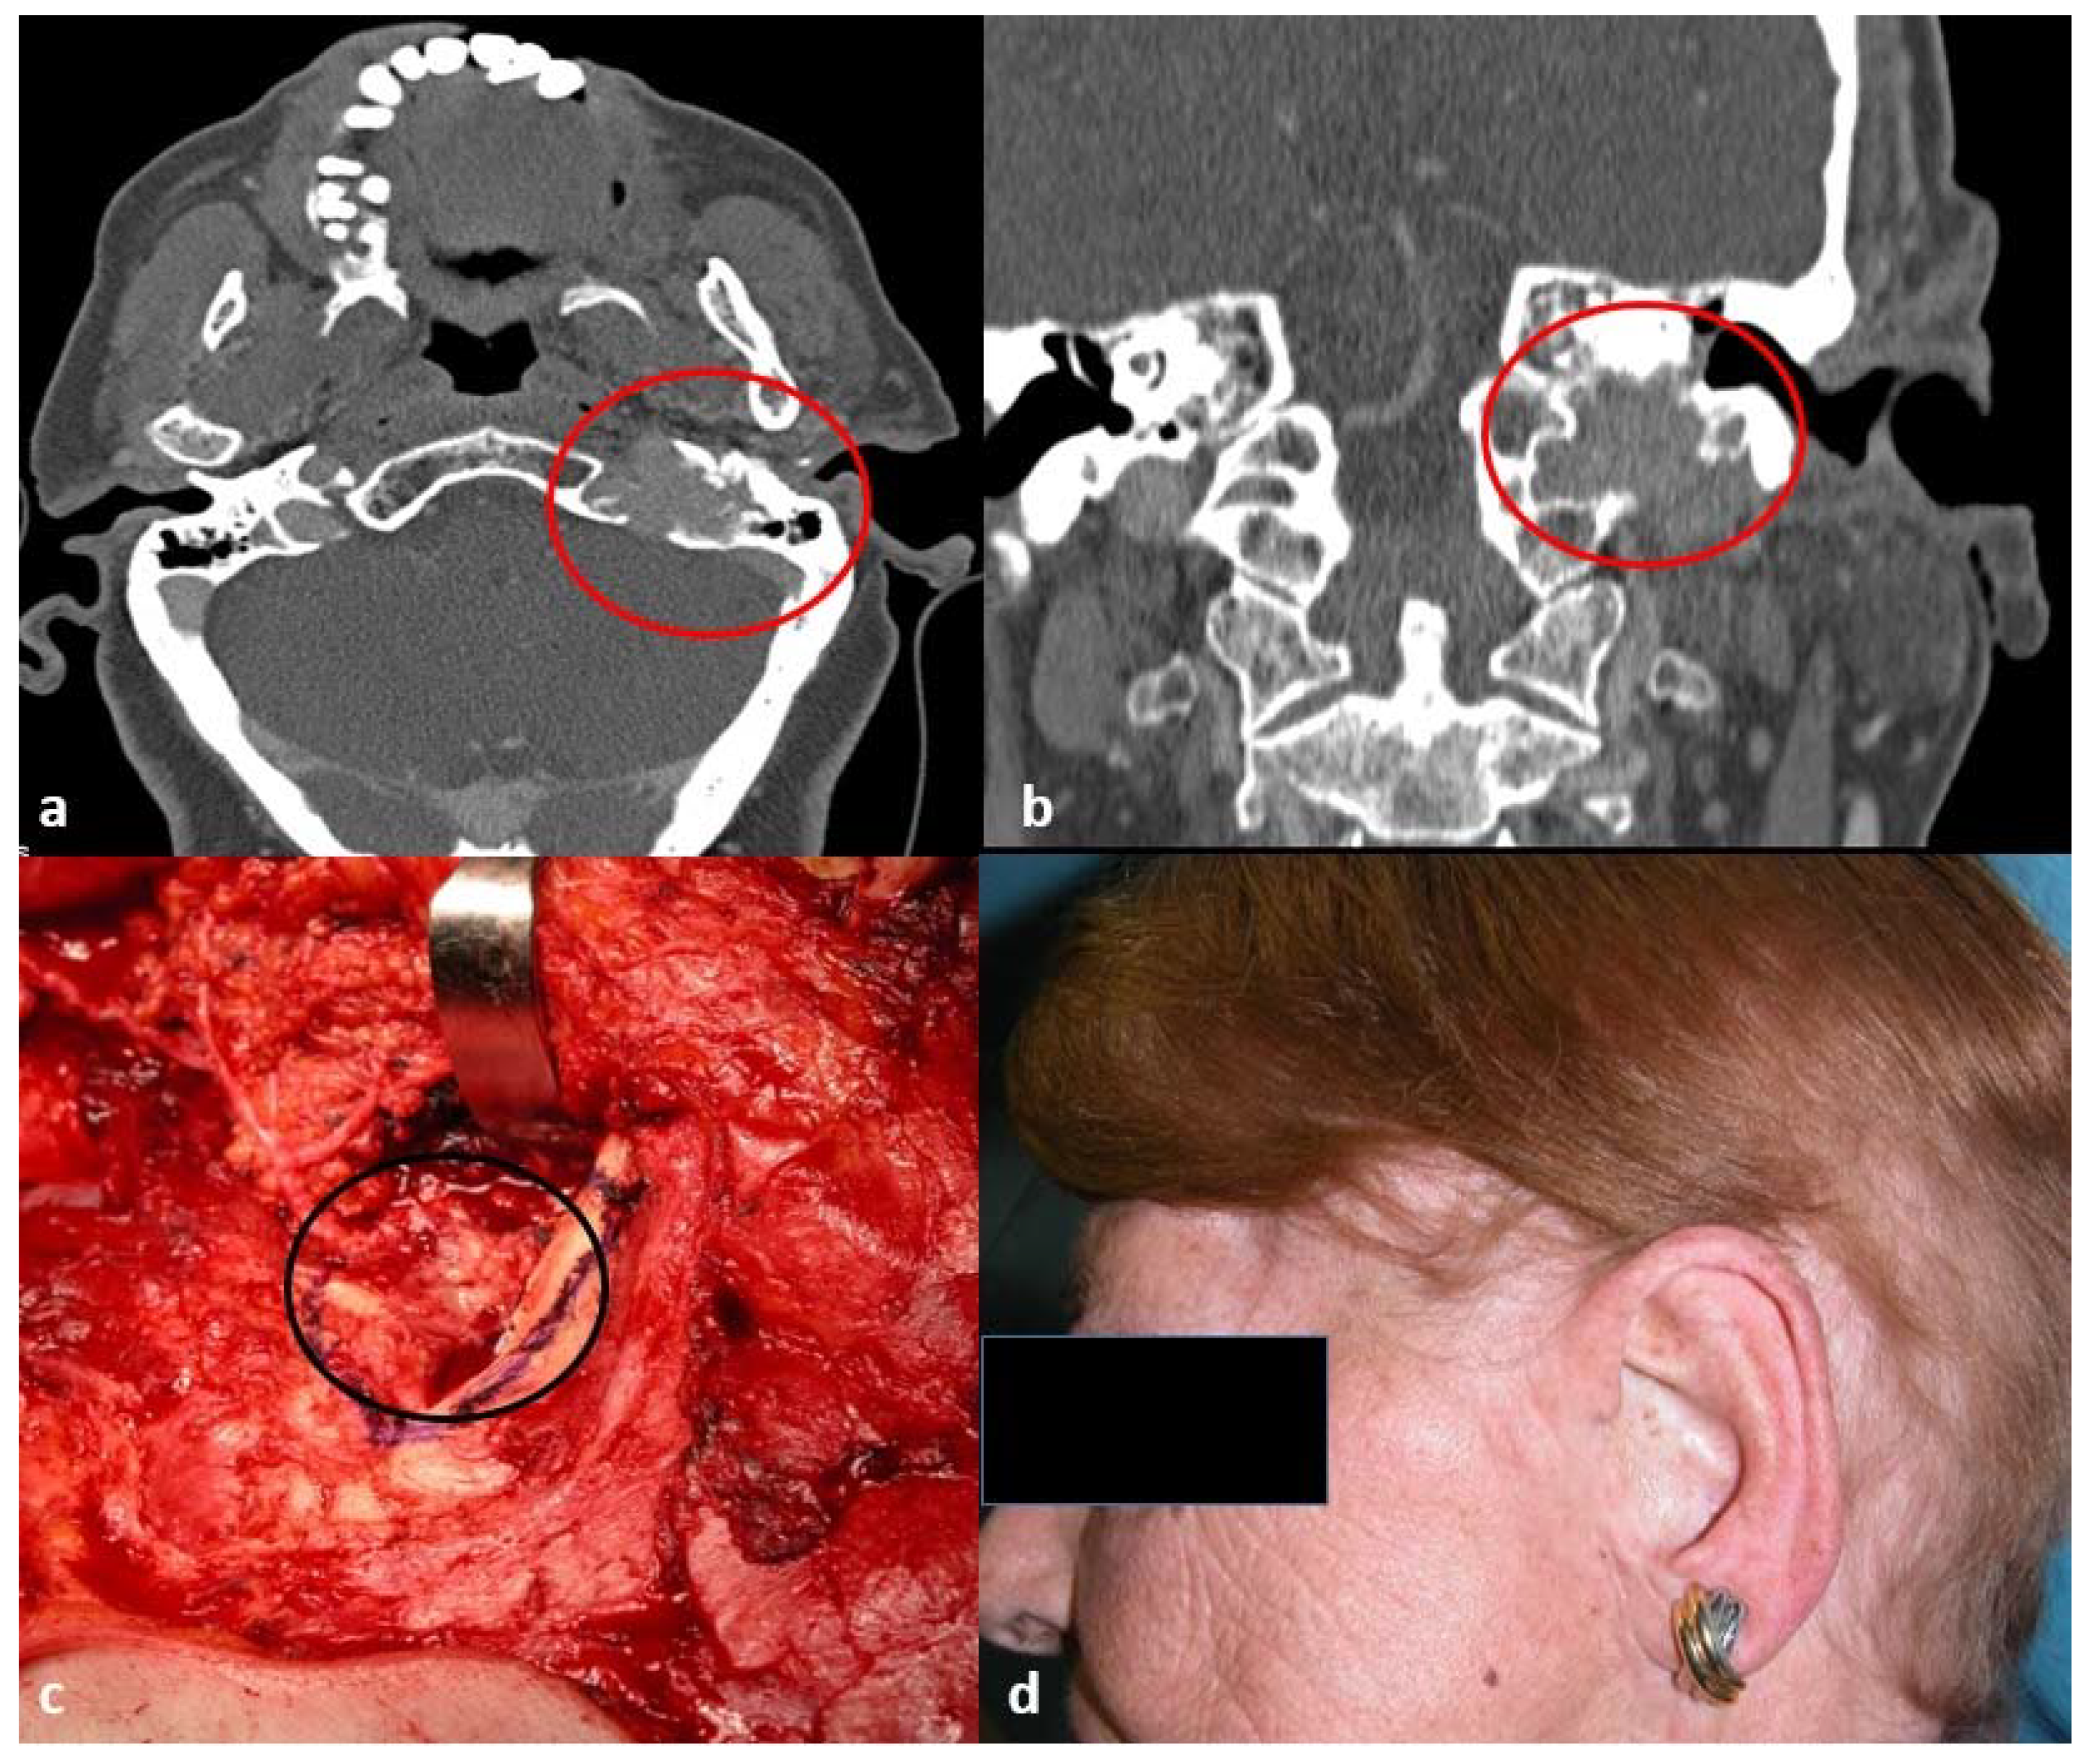

2.2. Tumor Assessment and Treatment

- Cristalli, G.; Mercante, G.; Marucci, L.; Soriani, A.; Telera, S.; Spriano, G. Intraoperative radiation therapy as adjuvant treatment in locally advanced stage tumours involving the middle ear: A hypothesis-generating retrospective study. Acta Otorhinolaryngol. Ital. 2016, 36, 85–90. [Google Scholar] [PubMed]